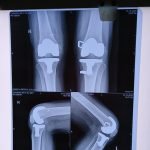

- Robotic Joint Replacement

- Knee Replacement Surgery